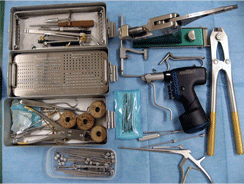

骨折の治療は、非観血的固定、骨プレート固定 、ピン・ワイヤー固定、創外固定など様々ですが、骨折部位や骨折の形状、患者さんの年齢や飼育環境、性格等を考慮し治療法を決定します。

骨折の治療や関節の手術などの整形外科は、特殊な器具や技術が必要であり、動物病院としてはなかなか厄介な分野なのかもしれません。

当院獣医師(森 昌人)は骨折治療の世界的基準であるAO/ASIF(Association for the Study of Internal Fixation)の基礎コース・応用コースを受講しており、この原理に従った骨折治療を行っております。